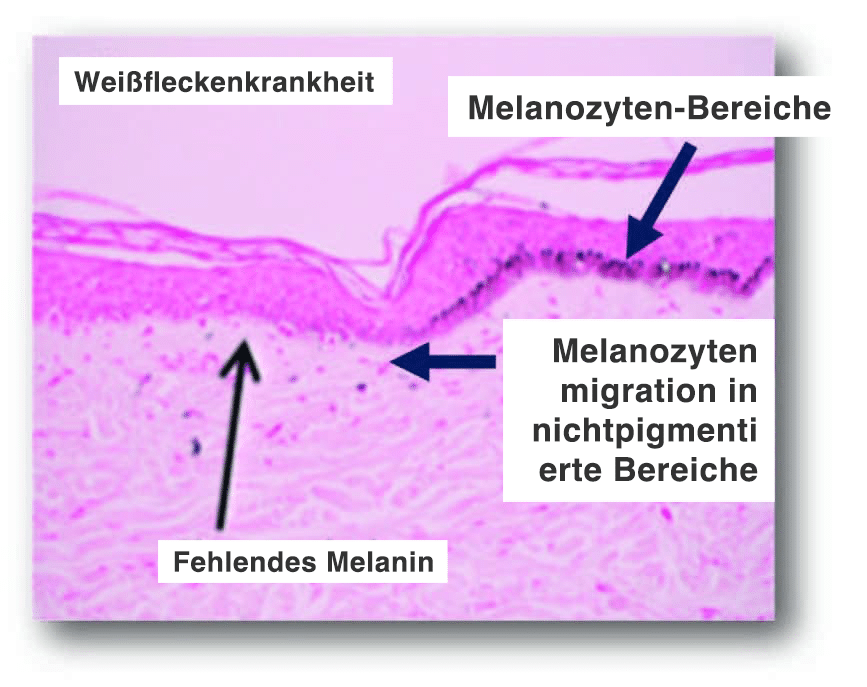

Hypopigmentierte Flecken

Wirkmechanismus:

- Induzieren der Aktivierung, Migration und/oder Proliferation von Melanozyten in hypopigmentierte Bereiche in der dermal-epidermalen Junktionszone (DEJ). Dieser flache Dermisbereich ist die Zieltiefe.

- Darüber hinaus stimuliert ein mechanisches Trauma die Migration der Melanozyten von den pigmentierten zu den unpigmentierten Bereichen.

- Das Microneedling kann die Anzahl der Pigmentzellen erhöhen und eine höhere Pigmentproduktion stimulieren

- Studien in der Literatur deuten darauf hin, dass 6 oder mehr Behandlungen erforderlich sein können, damit eine Verbesserung erkennbar ist

Stimulates melanocyte migration to restore pigment and smooth rolling scars.

Die Mikrokanäle bieten Raum für die Melanozyten, um in nichtpigmentierte Bereiche zu wandern